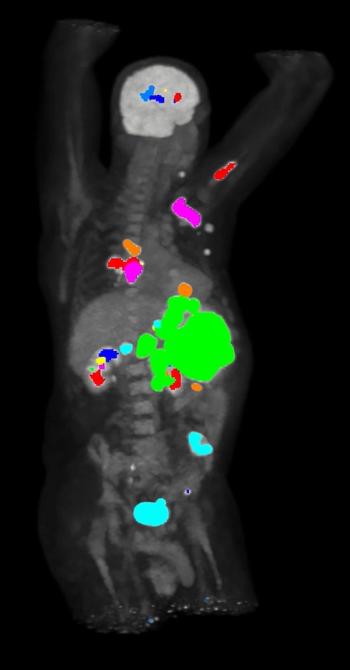

The iPETcertum software reportedly provides automated segmentation and enhanced visualization of regions of interest on PET scans with a single click.